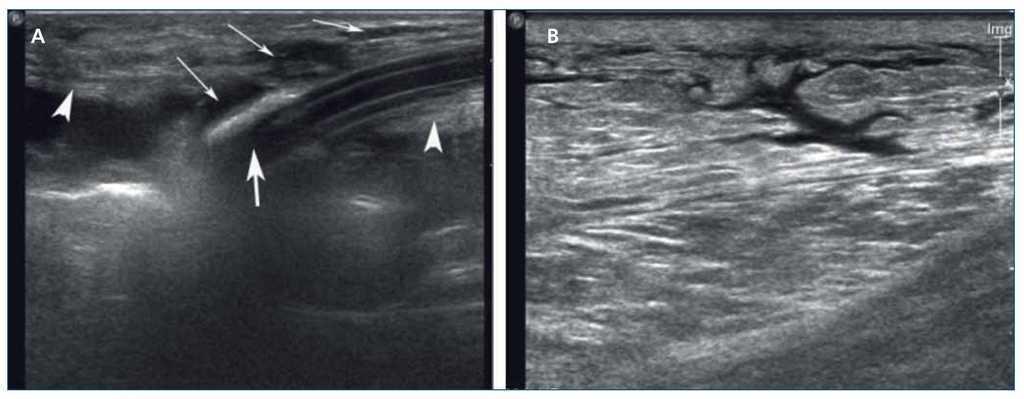

La fuga o escape peritoneal se define como la salida de líquido de la cavidad peritoneal. La prevalencia varía entre un 1 % y un 27 %2. Puede afectar a la zona pericatéter o a la pared abdominal en pacientes con hernias o con antecedentes de cirugía abdominal. Los factores identificados con la fuga de líquido de diálisis están relacionados con la técnica de inserción del catéter, el tipo de DP y los defectos de la pared abdominal3. El factor asociado más importante con fugas pericatéter es la mala colocación del dacron interno en la profundidad del músculo recto4 y no en el área subaponeurótica. Los síntomas clínicos descritos asociados a la aparición de fugas son baja ultrafiltración, presencia de tumoración o edema subcutáneo abdominal, salida de efluente pericatéter o edema genital. Las fugas se identificaron con ecografía ante la aparición de los siguientes signos (figura 1):

Figura 1.Fuga peritoneal. A) Visión longitudinal del dacron interno (flecha gruesa) rodeado de una imagen hipoecoica (flechas finas) correspondiente a fuga de líquido peritoneal. El músculo recto (cabezas de flecha) está adelgazado y rasgado secundariamente a la rotura. B) Bandas hipoecoicas secundarias a edema del tejido celular subcutáneo por fuga de líquido.

A) Brecha entre la pared abdominal y el peritoneo (donde previamente hubo un catéter o en la zona de un procedimiento quirúrgico previo, hernia de línea media o de Spiegel).

B) Patrón ecográfico de edema en el tejido graso subcutáneo, que podría estar asociado con el líquido que rodea el catéter y el dacron interno. Cuando existía una movilidad importante del dacron interno o se demostraba bastante líquido alrededor de este, era considerado como signo de mal pronóstico para el tratamiento conservador. La ventaja de la ecografía sobre el peritoneograma es que localiza el lugar exacto de la fuga y el tamaño de esta, lo que permite orientar el mejor tratamiento: conservador o quirúrgico.